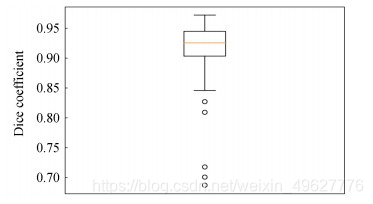

为解决假阳脑肿瘤病灶多的问题,结合病灶特征采用后处理方法进行假阳抑制,经过后处理的脑肿瘤测试集Dice指标分布如图 14所示.

图 14 结合后处理脑肿瘤测试集Dice指标分布

对比图 13和14可知,经过后处理的测试集中仅有3例样本远离集群点,而未经过后处理的有7例样本远离集群点,说明后处理方法切实可行.后处理的脑肿瘤检测可视化结果如图 15所示,可以看出经过后处理的输出结果有效地抑制了非脑肿瘤病灶的假阳区域,经过后处理的检测结果与标注的金标准拟合程度更高.

有无增加后处理方法的测试集脑肿瘤检测其三种评价指标如表 2所示,经过后处理方法的Dice、SN和SE可以达到0.926 7、0.928 1和0.997 7,较未经后处理方法的结果分别提升了0.94%、2.45%和0.13%,进一步验证本文方法的有效性.